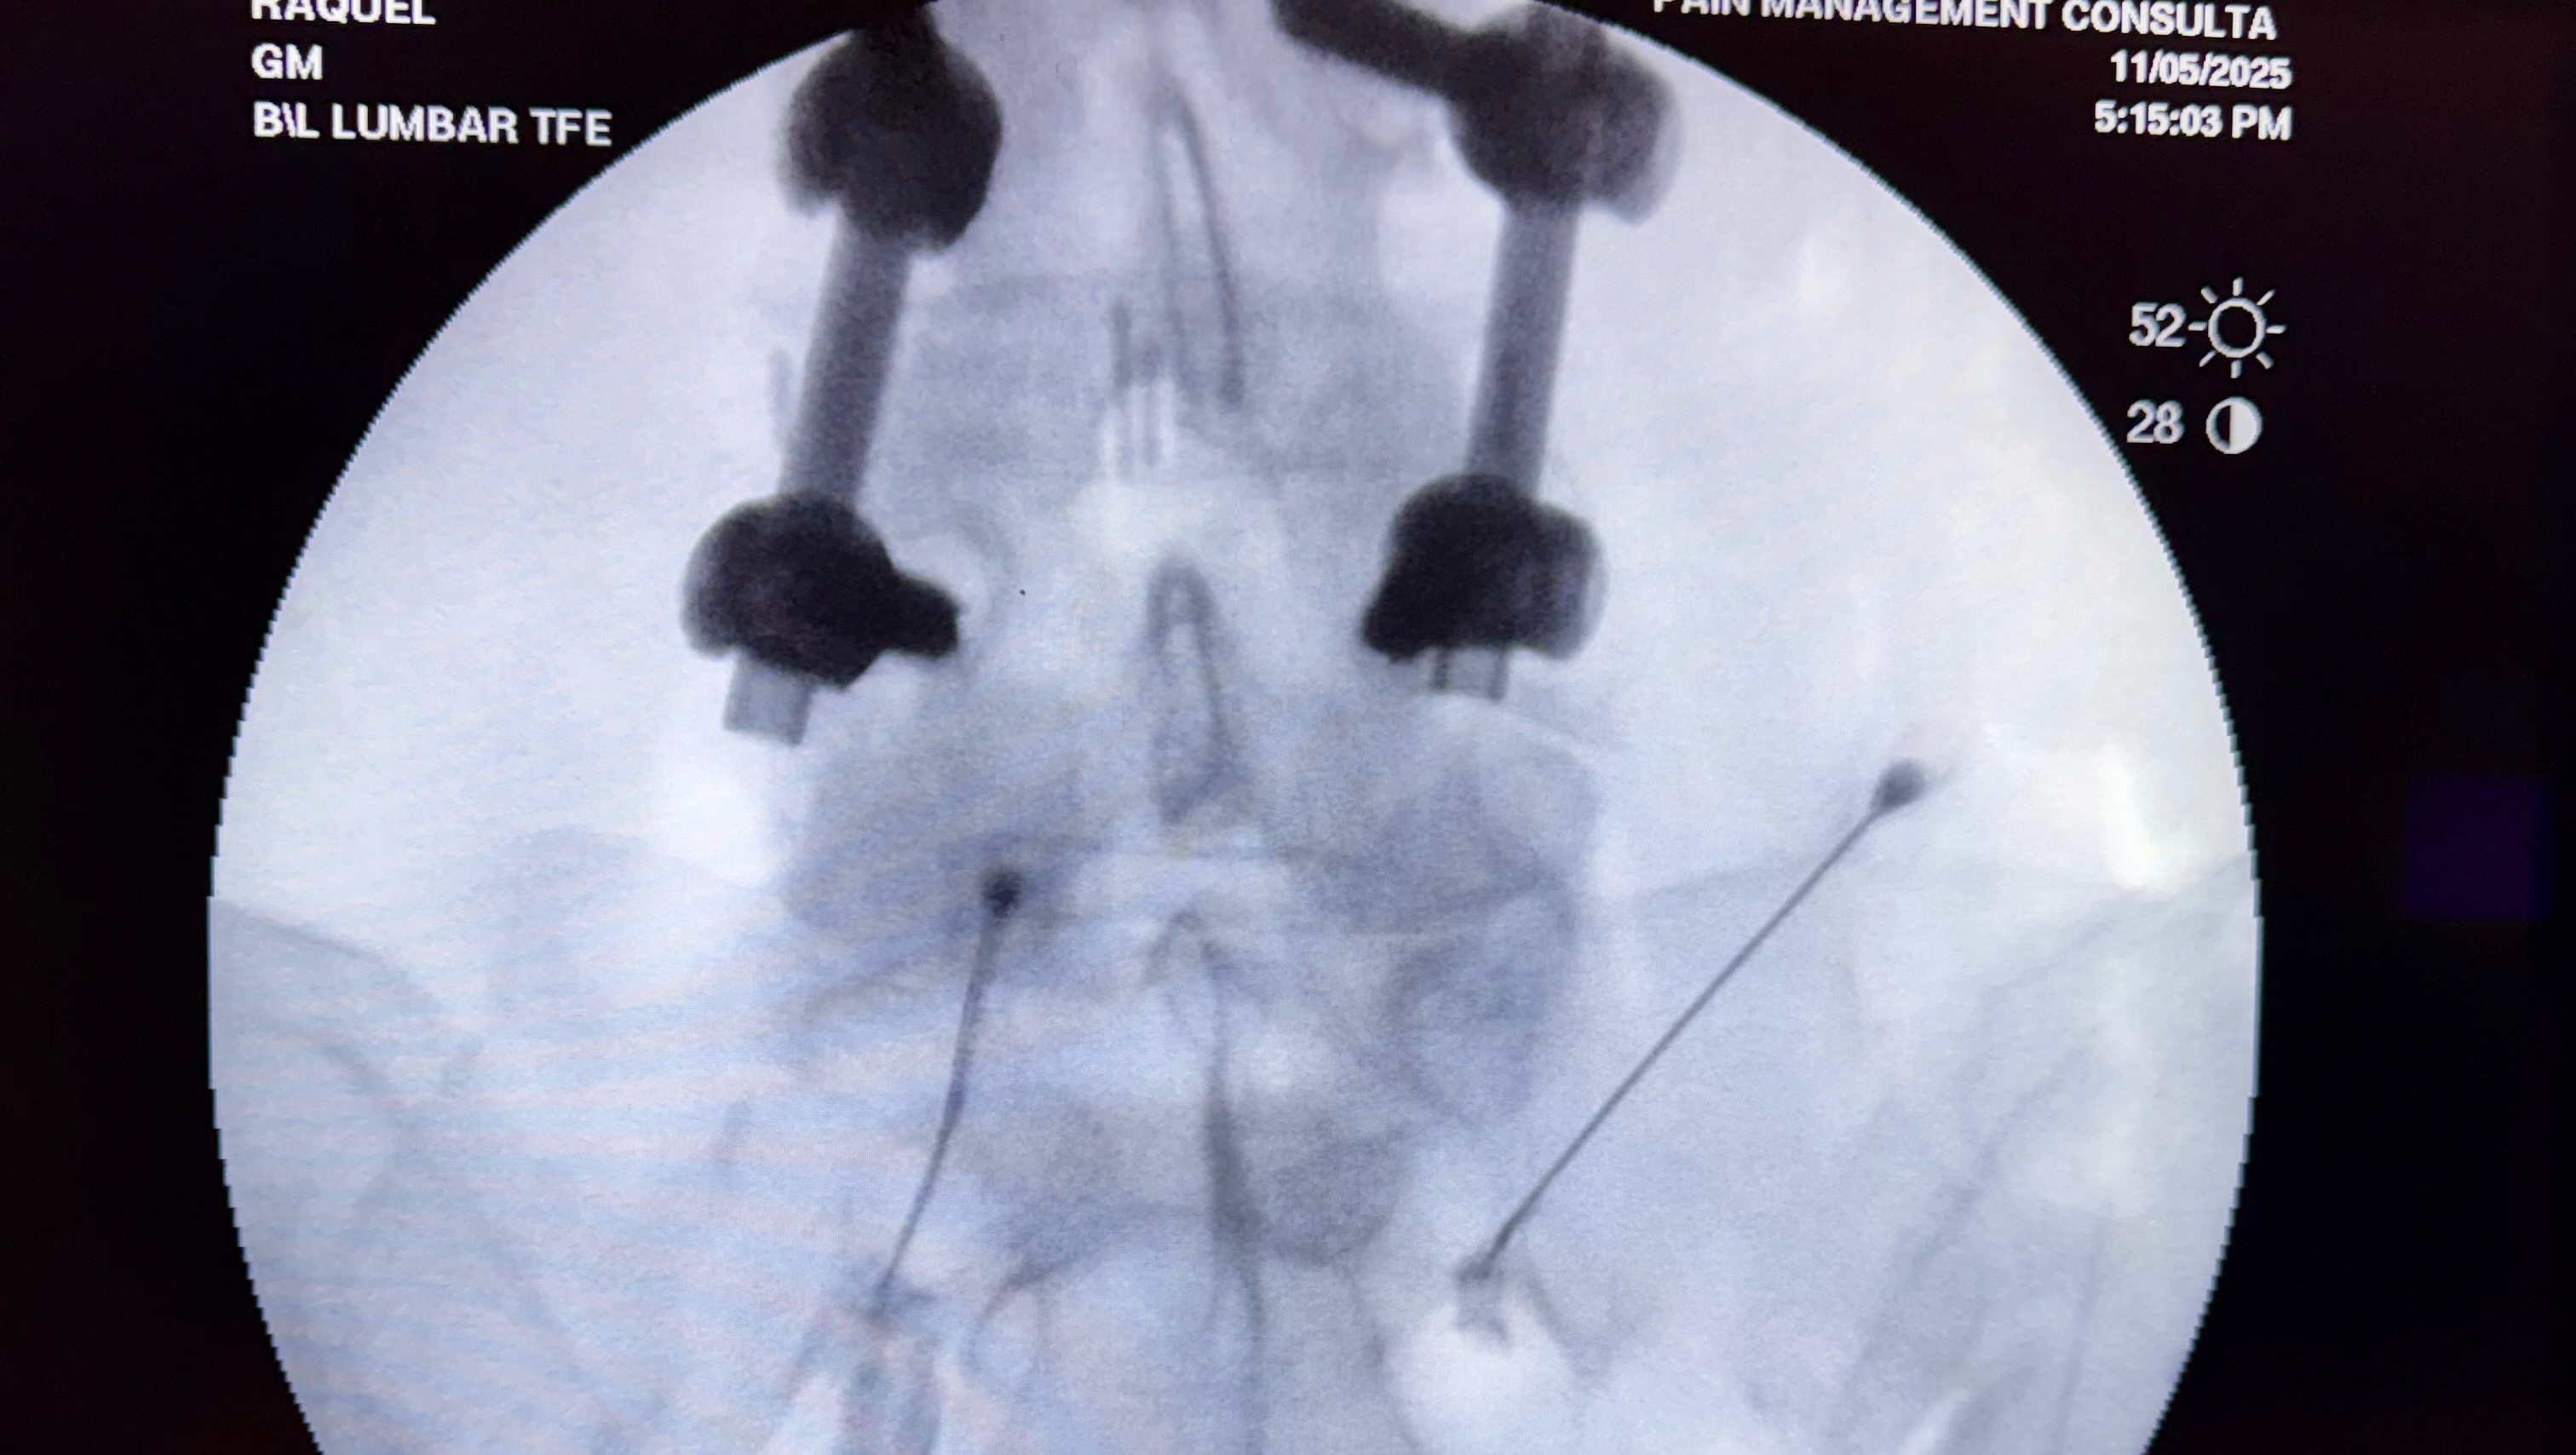

- She fell 8 yrs ago and seriously damaged her neck and lumbar spine. She has had 2 spine surgeries across 4 vertebrae as a result. Cervical disk replacements and lumbar fusion. The degenerative condition associated with that has progressed gradually but more so the last couple years and she is now approaching paralysis if she don’t get the right treatments. She suffers from muscle atrophy, weakness, pain and tremors. She is no longer independent and needs help doing almost everything and cannot walk on her own. She is one tough lady.